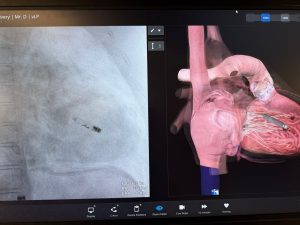

Imagen de un marcapasos sin cable («leadless») impactado en un corazón

A esto se suma otra de las innovaciones que generó gran interés en París: los marcapasos sin cables. “Son dispositivos muy pequeños que se implantan directamente dentro del corazón con una especie de resorte, y que cumplen la función de marcapasos. A pesar de su tamaño -como la falange de un dedo de la mano-, tienen una durabilidad de entre diez y doce años”, explicó el especialista.

Estos dispositivos, conocidos como “leadless”, representan un cambio significativo respecto de los sistemas tradicionales, al reducir complicaciones asociadas a cables y mejorar la recuperación del paciente.